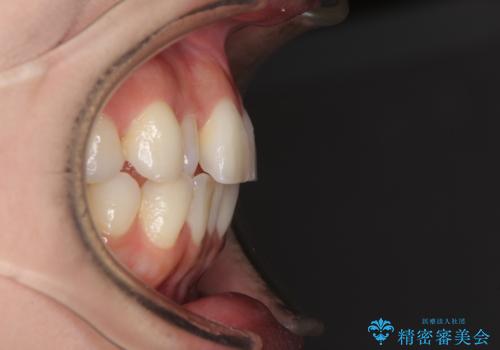

前歯のクロスバイト インビザラインによる矯正治療

- 上下のクロスバイトと前歯のデコボコを気にして来院された患者様です。

インビザラインを用い、IPR(歯と歯の間を削る)と歯列全体を拡大させることで、歯並びを整えていくこととしました。